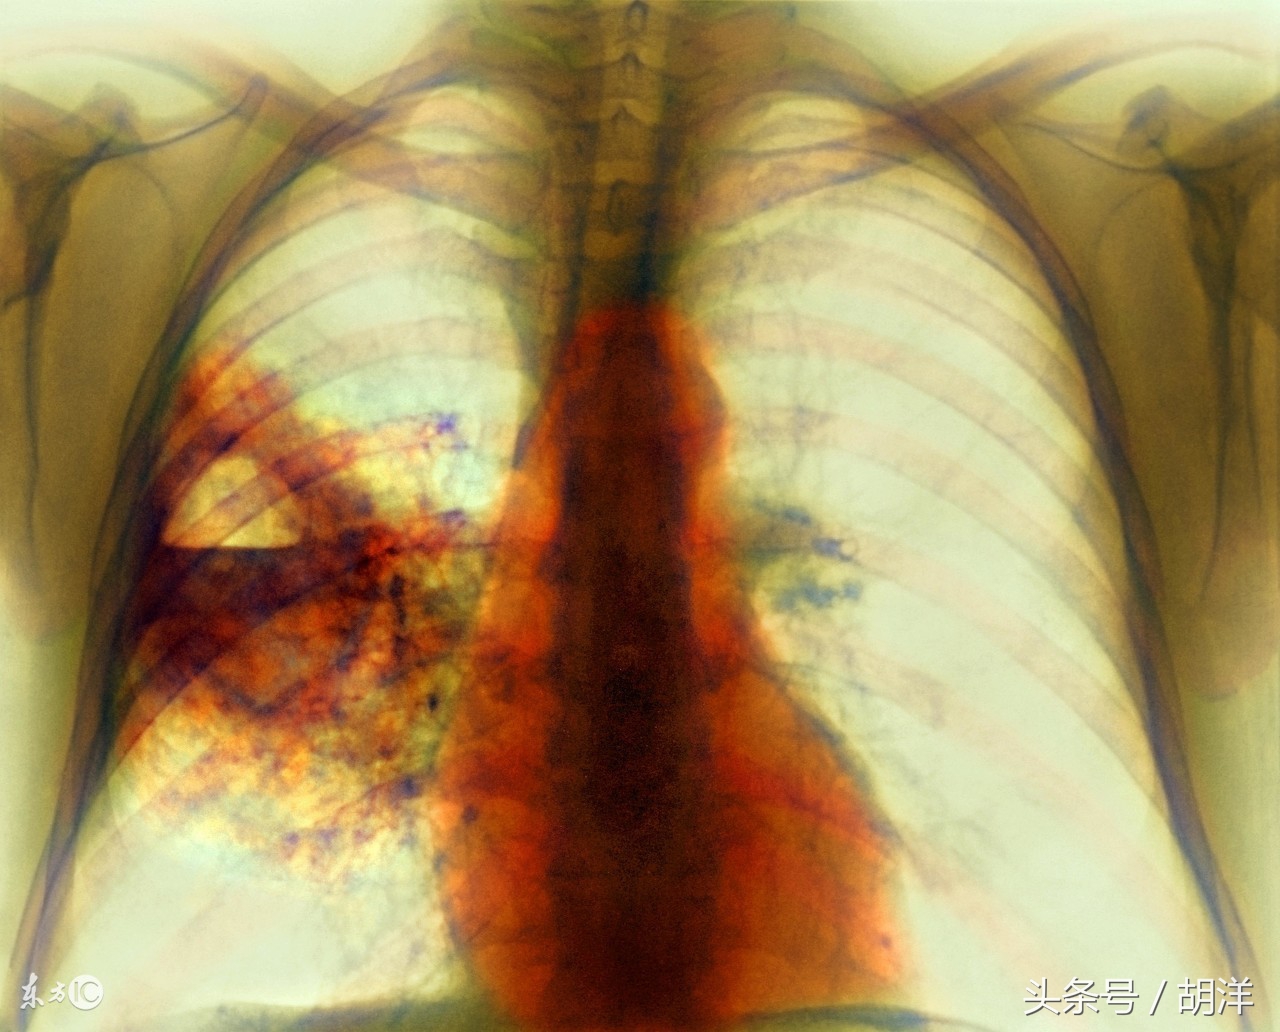

肺脓肿是造成肺部空洞的多种疾病之一

厌氧菌具有极大的破坏力,感染肺组织后很容易造成坏死,坏死的组织会形成浓痰排出体外,肺上就会形成一个空洞,空洞里不是干的,会积存一些脓液,这个是肺脓肿的特征性表现,其他会形成肺空洞的疾病还有肺癌,肺结核等,是临床上常常需要鉴别的三大疾病。